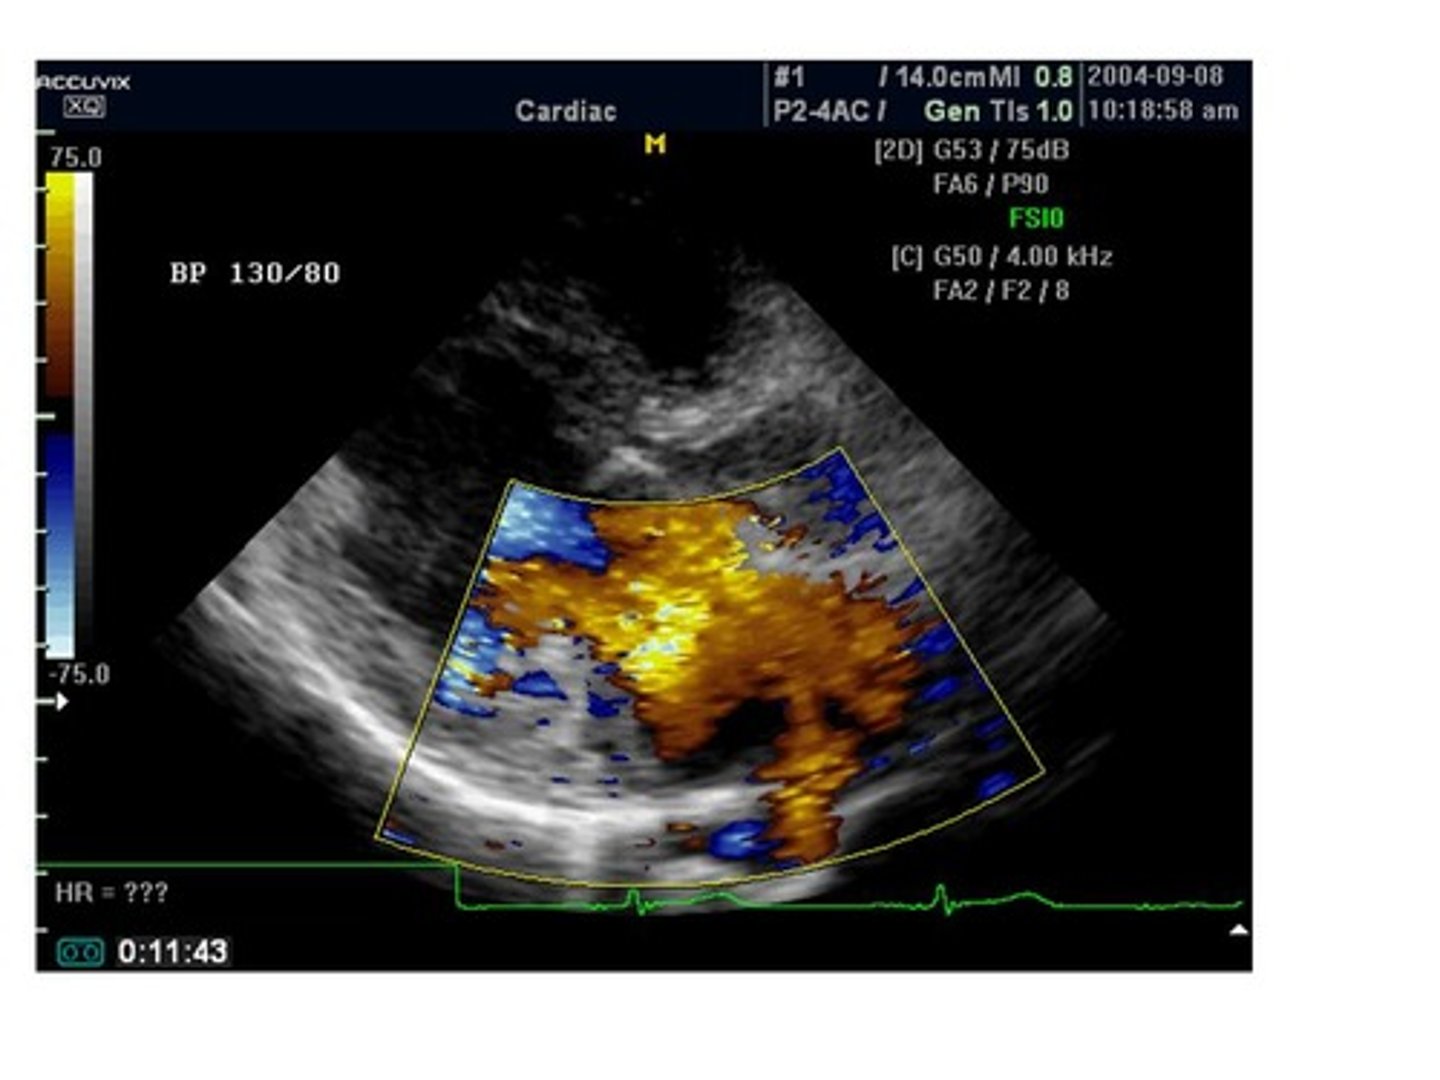

Looking at the color map on the image, the red color represents:

flow toward the transducer

flow away from the transducer

This image is demonstrating which type of color flow?

normal color flow

disturbed flow

spontaneous flow

steady flow

The blue color is demonstrating which of the following?

the transducer has nothing to do with the direction of flow